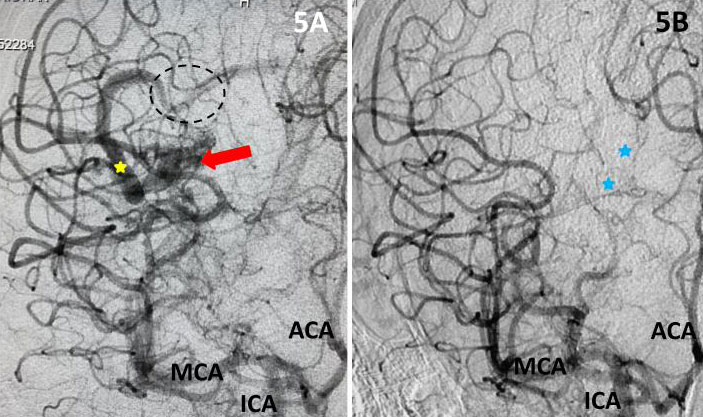

The patient was taken to the angio-suite where an angiogram confirmed a high flow, high pressure AVM fed primarily by the posterior cerebral artery with a small collateral from the middle cerebral artery (Fig 2 and 3). The AVM drained into a tortuous, partially occluded and stenotic single draining vein.

Fig 2. AP view, mid-arterial phase of a right internal carotid artery (ICA) injection. The large tortuous draining vein (yellow star) with the suggestion of clot (dotted circle) can be seen. AVM nidus (red arrow), MCA (middle cerebral artery, ACA (anterior cerebral artery).

Fig 3. Lateral view, late-arterial phase of a right internal carotid artery (ICA) injection. Filling of the AMV (red arrow) by the fetal posterior cerebral artery (PCA) and small middle cerebral artery feeder (blue arrow). The large tortuous draining vein (yellow star) with venous stenosis and the suggestion of clot (dotted circle) can be seen.